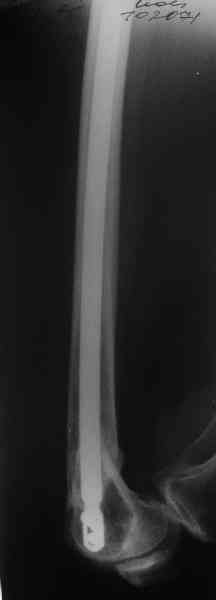

А в чем проблемы? Пример в приложении.

Насчет снимка Вами представленного - смотрится оч красиво, еще бы на функцию узнать...

I> Насчет снимка Вами представленного - смотрится оч красиво, еще бы на

I> функцию узнать...

В приложении функциональные снимки в 3 мес. и в 1 год.